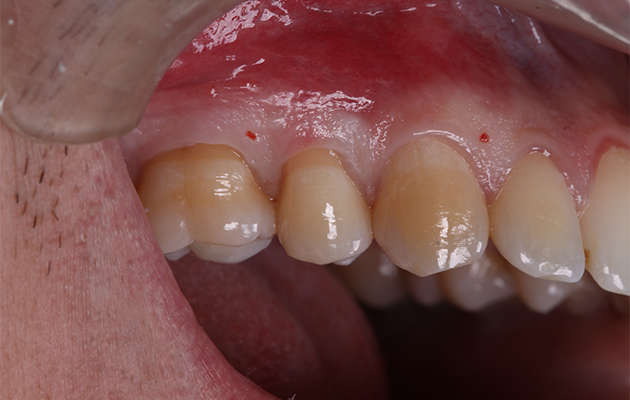

5 | Condição clínica pré-cirúrgica.